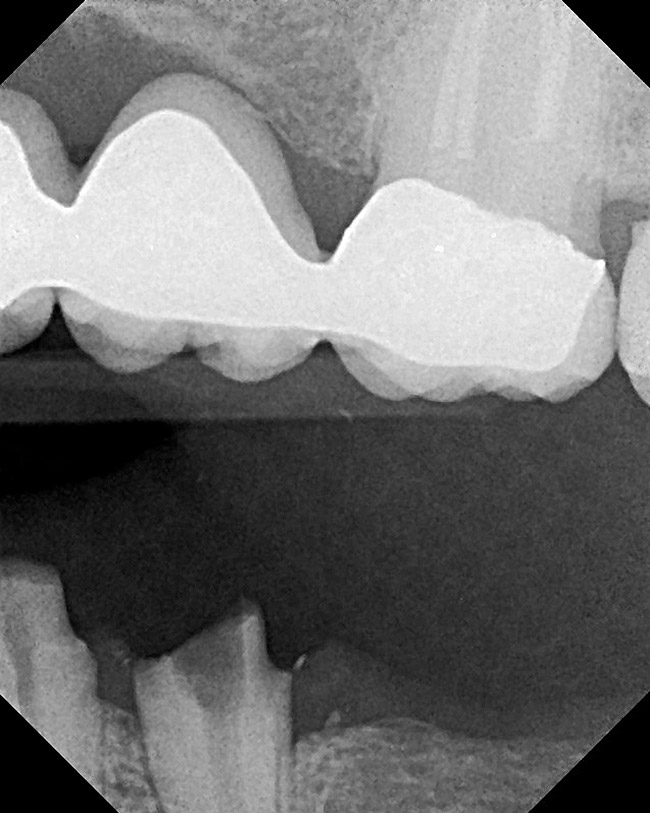

Figure 16  After initial positioning of the bone, keeping the tip of the laser in intimate contact with the root surface, a slight troughing of the bone was seen on radiographic examination.

Figure 16

Figure 18  Radiographic examination after smoothing and blending of the bony surfaces confirmed that the bone was smooth and the ledge was eliminated.

Figure 18